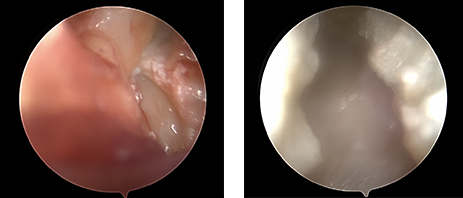

미세내시경 유리술은 부분 마취하에 피부 절개 없이 약 2mm 정도의 작은 내시경 포털만을 이용하여 병변에 접근합니다. 때문에 주변조직 손상 없이 손목터널의 뚜껑 부분인 횡수근인대만을 선택적으로 절개하여 터널을 넓혀주는 것이 가능하므로 환자부담이 현저히 줄어들었습니다.

therapy therapy

좌/우로 나눠진 횡수근인대는 시간이 지남에 따라 자연스럽게 연결되면서 결과적으로 손목터널이 넓어지는 효과를 보이게 됩니다.